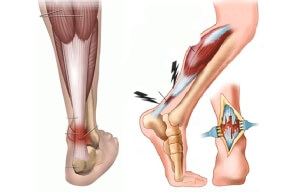

Признаки травмы

Симптоматика при повреждении связок всегда одинакова, различается только по степени проявления болевых ощущений, которые зависят от степени их травмирования:

- При получении травмы возникает острая боль местного характера.

- Наличие проявления припухлости стопы и голени.

- В месте ушиба может возникнуть гематома.

- При местном обследовании ноги возникают боли различной степени, чем ближе к очагу повреждения, тем боль становится сильнее.

- Возможность передвижения может быть частично потеряна человеком, получившем травму голеностопного сустава.

При диагностировании полного разрыва связок больному, чаще, назначается оперативное лечение.

При котором поврежденные связки сшиваются, или вставляются на их место импланты. После проведенной операции пациенту накладывают гипс.

После снятия гипса, сразу человек бегать и прыгать не сможет, потребуется масса физиопроцедур, гимнастика в лечебных целях и время для реабилитации.